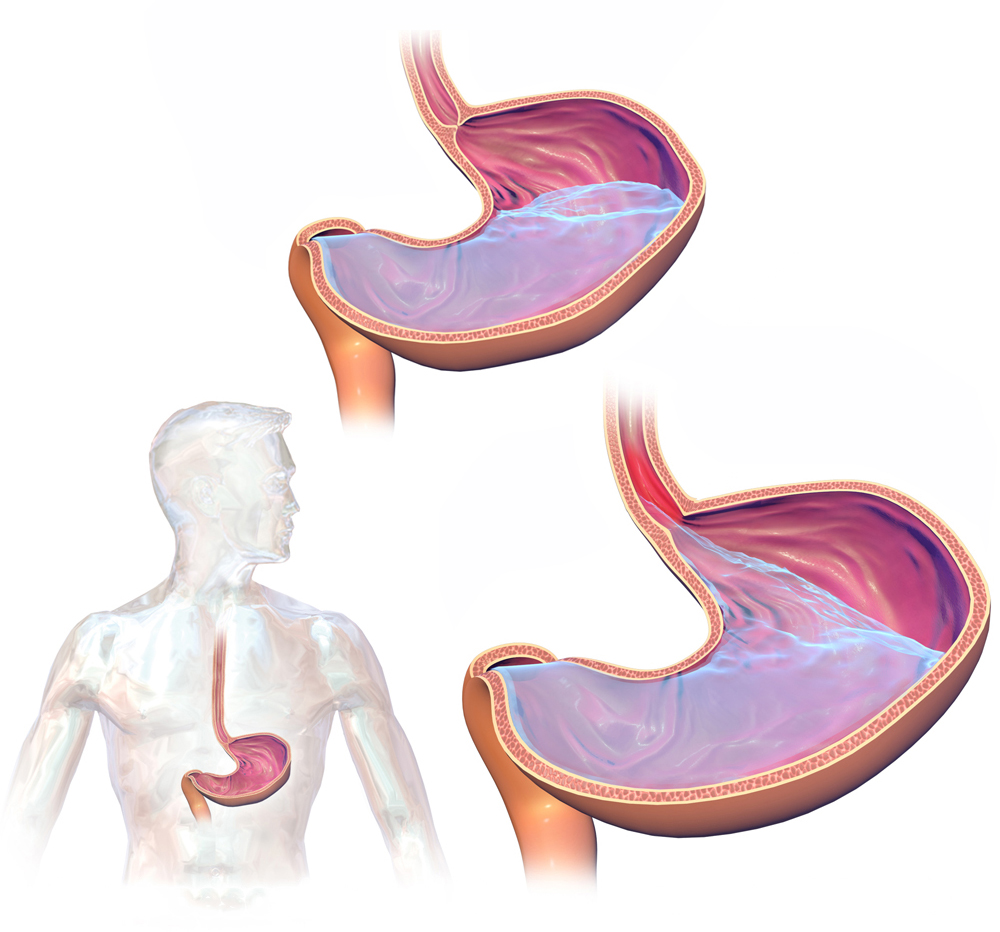

Una vez ingeridos los alimentos, empieza el proceso de digestión en nuestro estómago y se comienzan a secretar ácidos (ácido clorhídrico) para procesar la comida y adquirir los nutrieres que son tan valiosos para nuestro organismo. Existen barreras como el diafragma, Esfínter Esofágico Inferior (EEI) y la gravedad que evitan que el contenido gástrico se devuelva al esófago, que es el conducto que une nuestro estómago con la garganta, pero estas barreras se pueden debilitar en ciertas situaciones. Mientras estamos de pie o sentados el contenido gástrico se mantiene en su lugar, pero si nos acostamos en una superficie horizontal (decúbito) eliminamos la ayuda de la fuerza de gravedad y si el EEI que es la compuerta que separa el estomago del esófago no cierra completamente bien, que es algo muy común, pues pasa el contenido gástrico a nuestro esófago, y es lo que denominamos como Reflujo Gastroesofágico.

Si no lo has entendido aún, pues imagínate una botella con agua que no tiene la tapa bien puesta, mientras la botella se encuentra de pie o en forma vertical no se bota el agua, pero si viramos la botella y la ponemos acostada o de forma horizontal se empieza a verter el contenido, en este caso la botella seria el estomago y la tapa el Esfínter Esofágico Inferior (EEI).

Siguiendo donde nos habíamos quedado, el contenido gástrico trae consigo ácidos que se utilizan para la digestión de los alimentos, y estos al entrar en contacto con el esófago van a provocar daños en su mucosa que es la capa que lo recubre internamente. El Reflujo Gastroesofágico o popularmente conocido como Acidez puede provocar síntomas como la pirosis, que es la sensación de ardor o quemazón en el pecho (retroesternal). El otro síntoma que puede aparecer es la regurgitación, que es la sensación de los los líquidos o alimentos ingeridos suben por el esófago. Si este suceso se repite con el tiempo se vuelve algo crónico y puede dar lugar a otras afecciones como ulceras esofágicas o en un Esófago de Barrett.